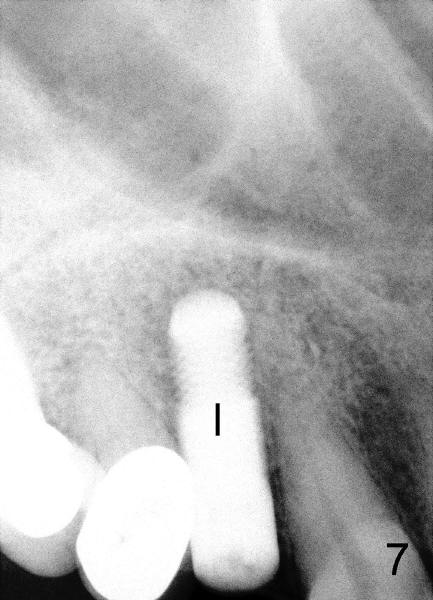

Sixty-eight year old healthy man has had multiple implants.  He readily accepted immediate implant when the tooth #5 had subgingival fracture of the lingual cusp (Fig.1).  A 5x20 mm Tatum screw implant was placed immediately after atraumatic extraction and bone expansion (Fig.2 I).  Implant rough surface was exposed buccally and lingually when the implant was placed equigingivally proximally.  Two buccal accessory incisions were made.  The flap was raised with scoring the periosteum underneath, advanced downward (as shown in Fig.3 arrow) and sutured to the lingual papilla.  The buccal aspect of the implant is covered, whereas the lingual rough surface remains partially exposed (Fig.4 arrow), assuming that the palatal mucoperiosteum is tough to advance even with release incisions.

Fig.7-9 are taken 3.5 months postop.  Buccal gingiva appears to have elevated (Fig.8 arrow, as compared to Fig.5 B).  The rough surface seems to have been partially covered by lingual gingiva (Fig.9 arrowheads, as compared to Fig.6).